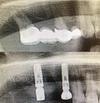

Periimplantitis